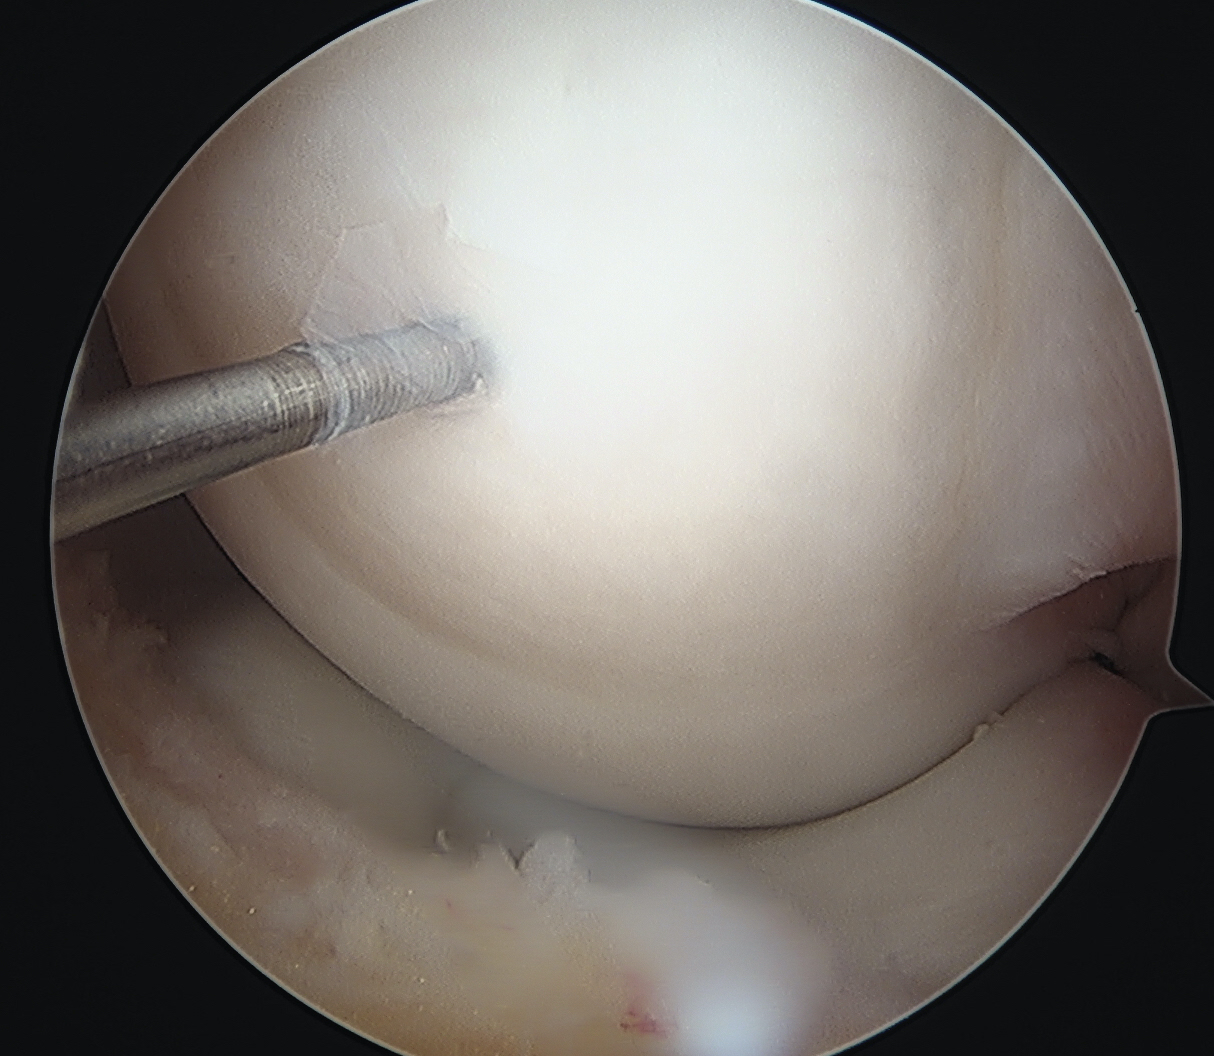

Flex and extend knee to place inferior / superior screws

- typically 2 - 3 screws maximum (3.5 mm)

- 22 - 26 mm long, want to stop short of growth plate

- ensure screw heads are buried under cartilage, but not too deep so they still engage fragment

- can microfracture with 1 mm k wire around screws